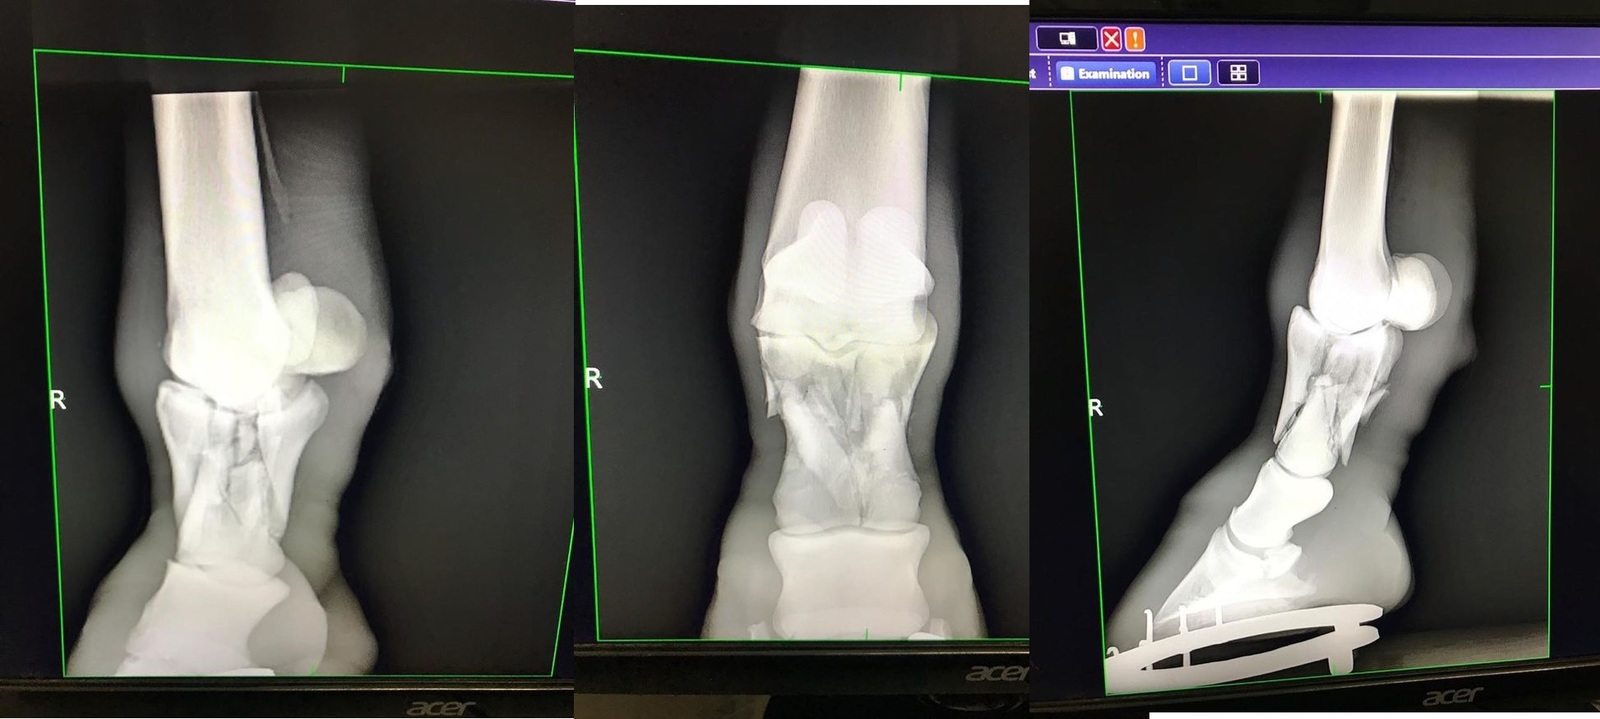

Снимки

Ногу собрали

Одним из последних ветеринарных достижений при лечении переломов у лошадей, является метод транскортикальной (чрезкостной) фиксации. Смысл такой фиксации заключается в том, что выше места перелома внутри кости временно ставят специальные металлические стержни, а потом всю конечность одевают в легкий и вместе с тем очень прочный полимерный гипс, в котором и закрепляют эти стержни. Таким образом, получается, что конечность лошади выше места перелома как бы подвешивается внутри гипсовой повязки. В результате этого лошадь получает возможность полностью опираться на сломанную конечность, так как весь ее вес при этом ложится только на здоровую кость и гипс, а поврежденный участок остается без нагрузки. Устанавливаются такие стержни под общим наркозом, как правило, одновременно с наложением гипса или при проведении операции по остеосинтезу. В настоящее время метод уже достаточно широко апробирован как за рубежом, так и у нас и помог спасти не одну лошадиную жизнь. Во многом, только благодаря транскортикальной фиксации у врачей появился шанс бороться за жизни лошадей даже при таких серьезных травмах, как полный перелом пястной или плюсневой костей. Источник 2009 год